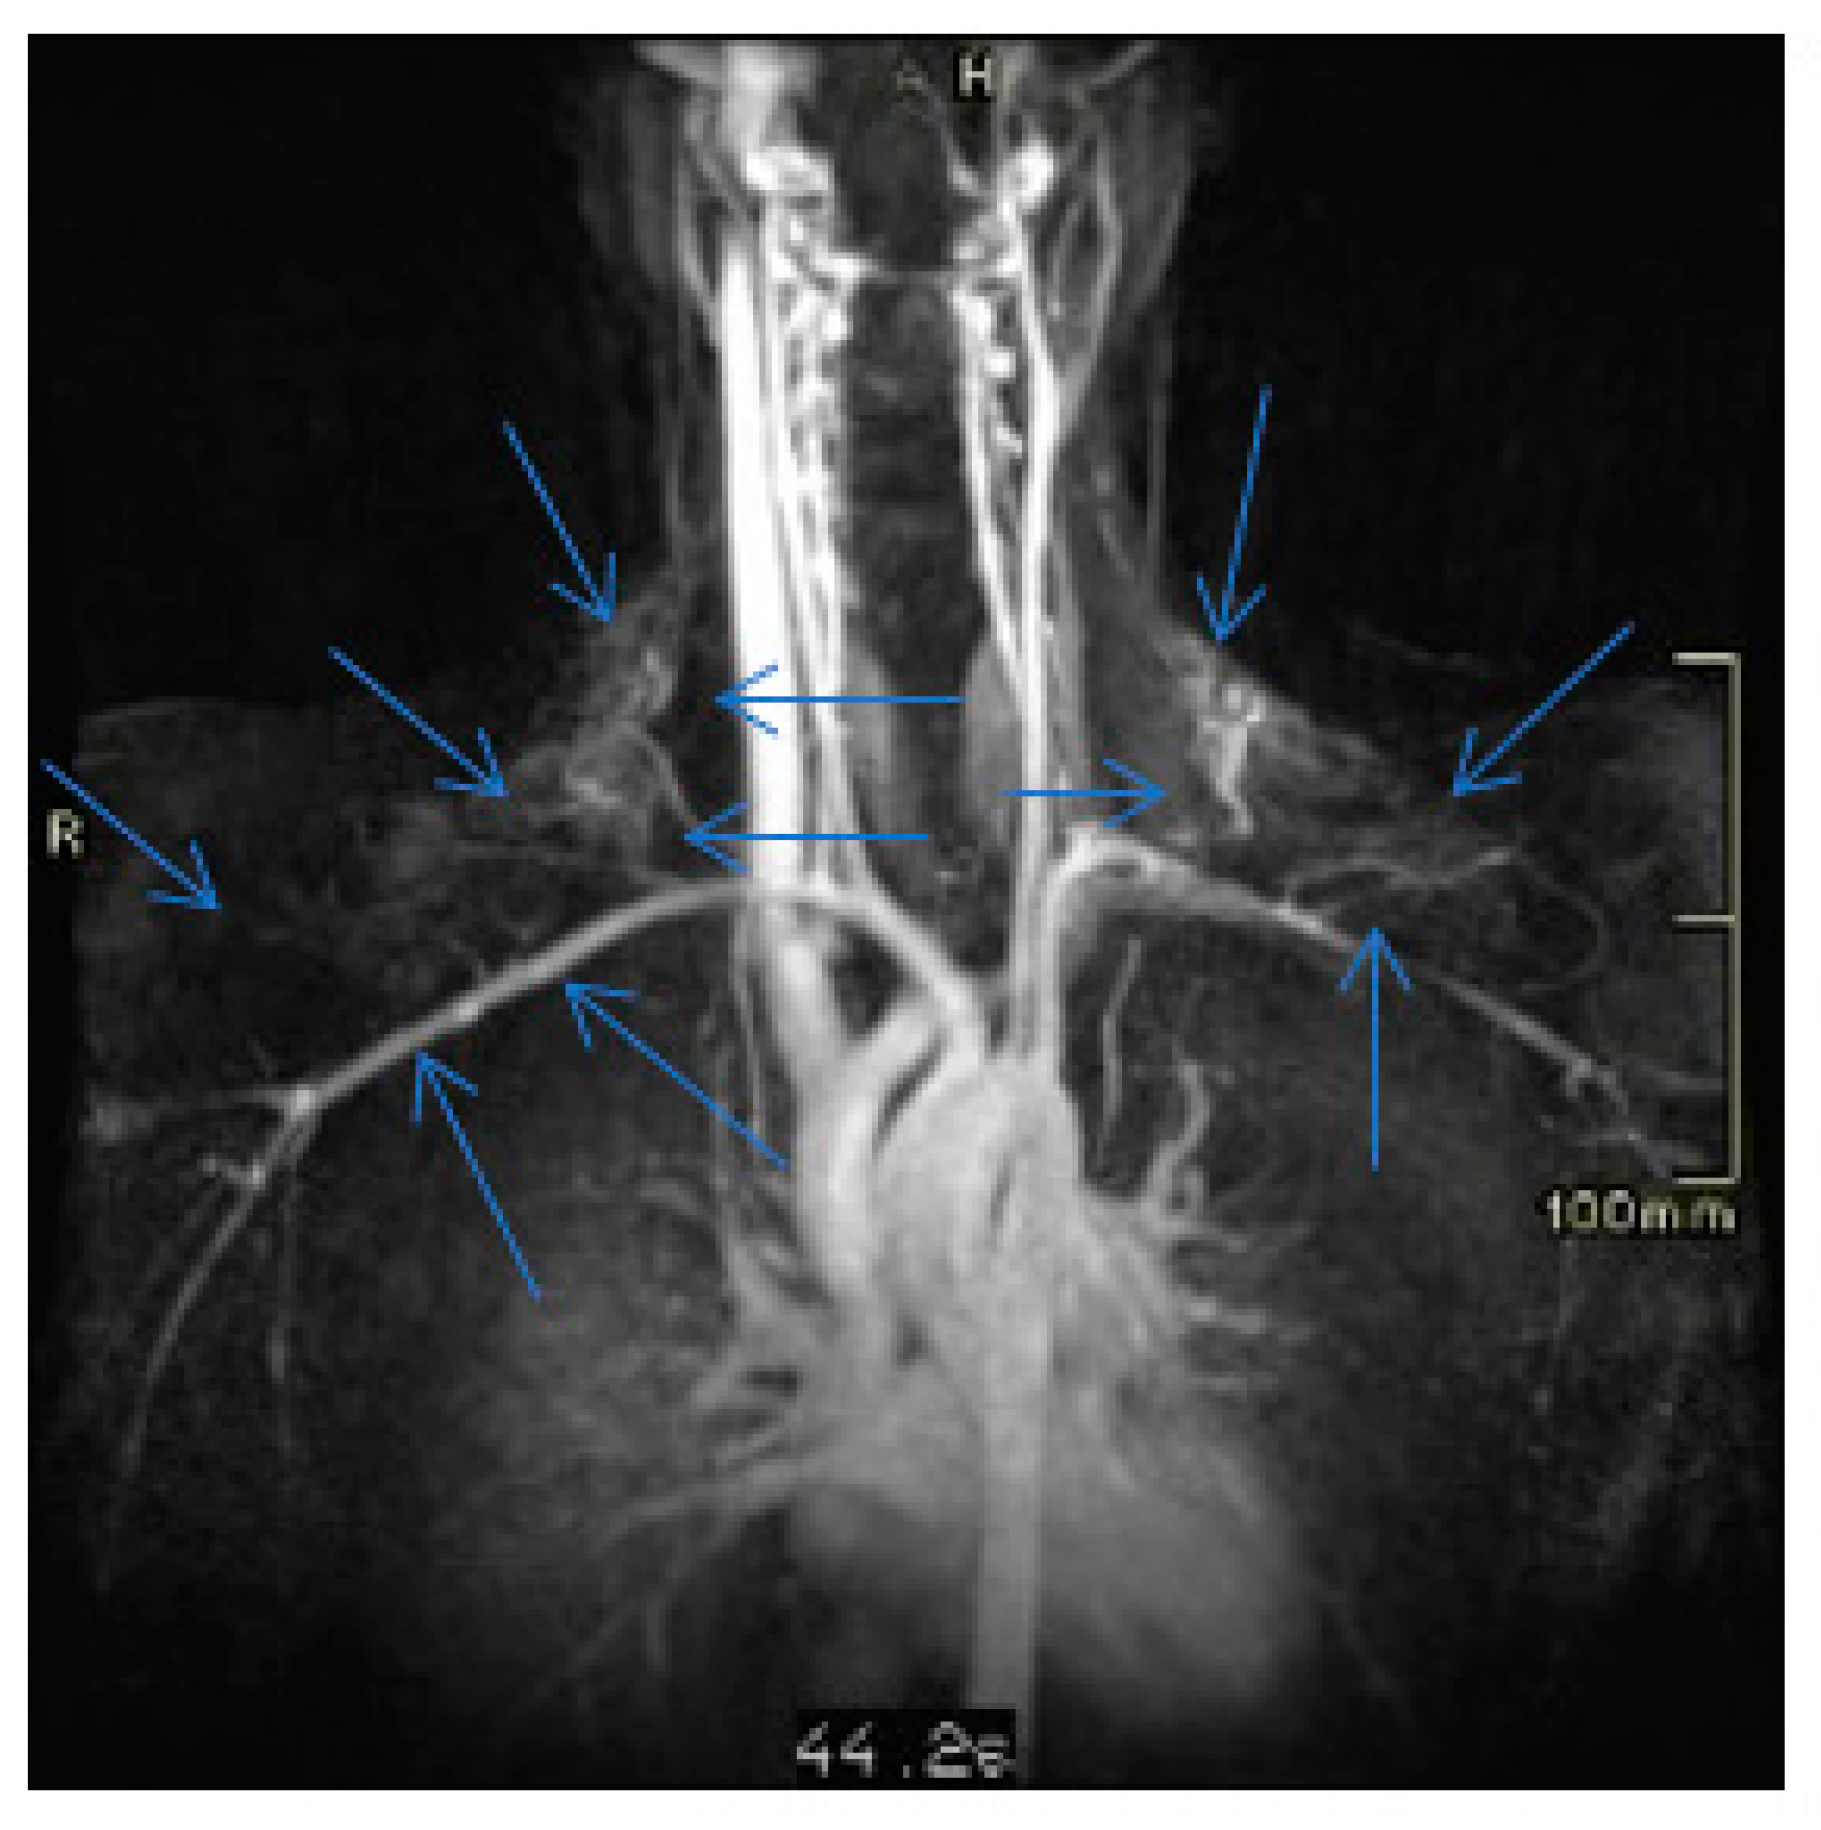

2. Case Presentation